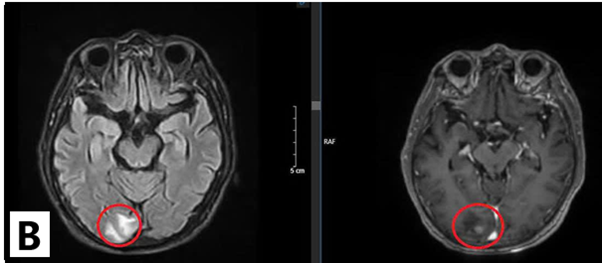

Chụp cộng hưởng từ sọ não: Nhu mô não vùng trên lều tiểu não có các nốt tổn thương nhu mô não dưới vỏ thuỳ trán trái, thùy đỉnh hai bên và thùy chẩm phải, đường kính ổ tổn thương lớn nhất 12mm, ngấm thuốc mạnh sau tiêm, có phù não rộng xung quanh.

Hình 2: Hình ảnh cộng hưởng từ sọ não: Các nốt tổn thương nhu mô não ngấm thuốc mạnh sau tiêm, có phù não rộng xung quanh (vòng tròn màu đỏ)(B: Thùy chẩm, A,C: Thùy đỉnh)